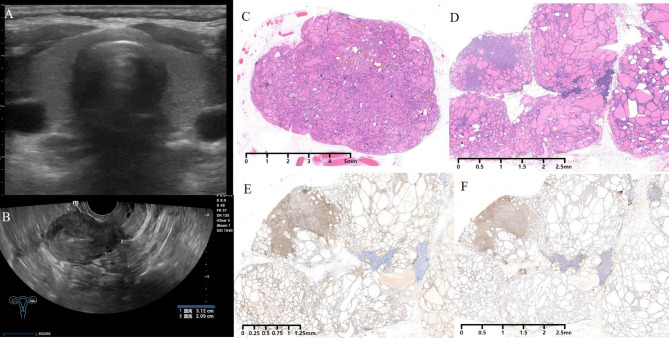

Case presentation: A 41-year-old Chinese woman underwent transabdominal left oophorectomy for a benign SO 18 years prior to presentation in the clinic. She was admitted to our institution for periodic medical examination after ultrasonography revealed a left pelvic mass. The patient underwent total abdominal hysterectomy, right salpingo-oophorectomy, and omentectomy, and multiple biopsies were taken from the omentum and mesentery. Pathology revealed peritoneal strumosis without evidence of malignancy from SO. Afterward, a total thyroidectomy was performed, and a histological examination revealed multinodular goiter. In total, 4400 MBq of 131I was administered, and lesion remission was confirmed. Finally, after 1 year of follow-up, the patient had no evidence of recurrence.